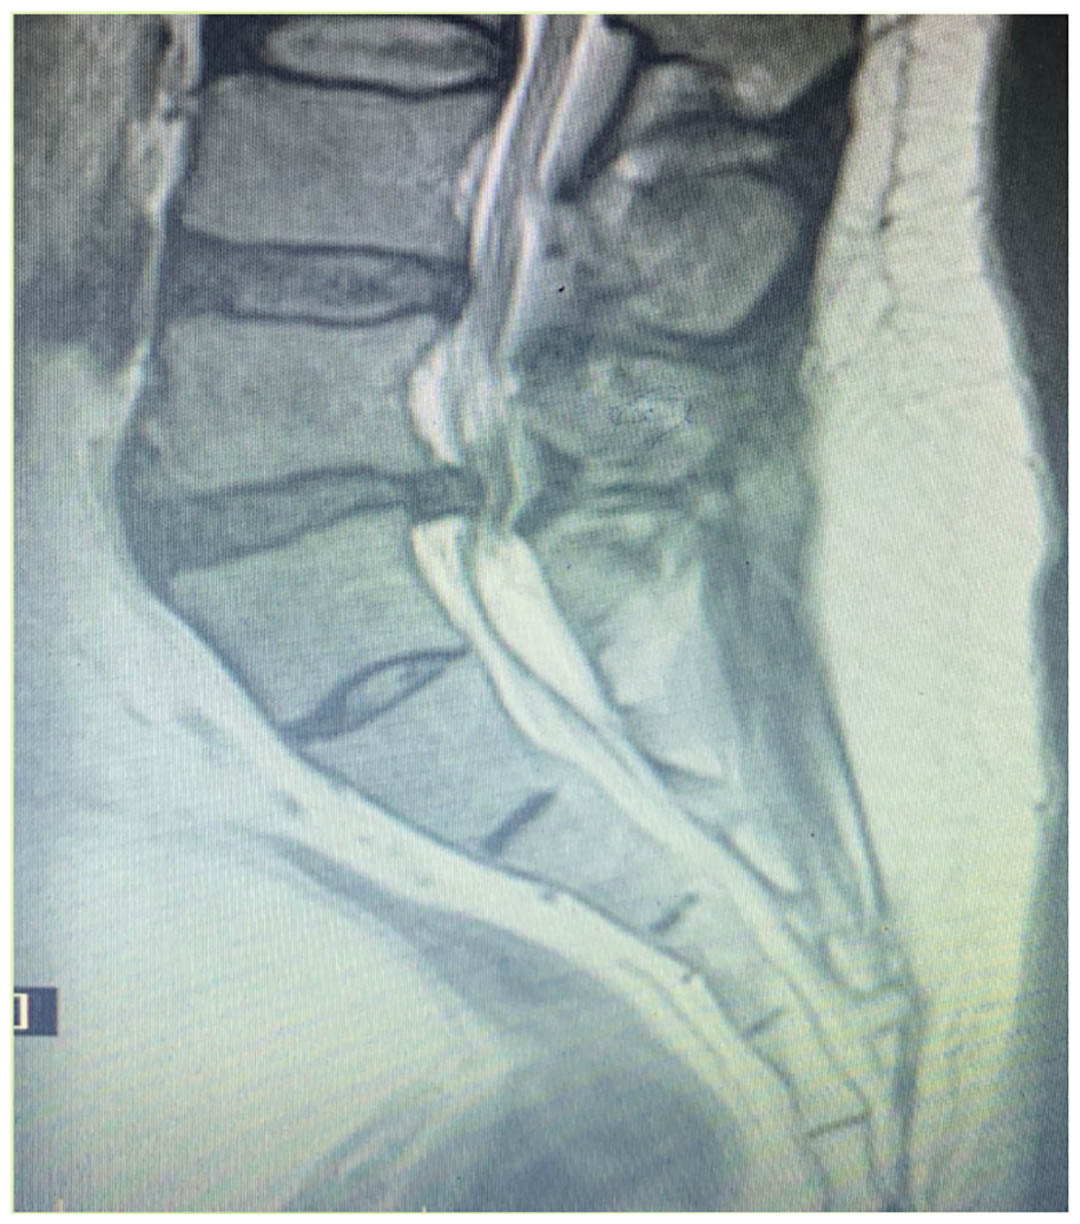

A 55 year old man presented to a  busy urologist with complains of poor stream and straining to pass urine of one week duration , he also reported loss of desire to void along with constipation. After a rapid preliminary examination he was started on 8 mg of  Silodosin and asked to came back with an USG KUB, uroflowmetry and urine analysis after 5 days.Two days later  patient presented to the emergency with painless retention of urine with vague back ache. After catherisation, 1 litre of urine was drained , USG KUB revealed a prostate of 35 gm with median lobe and a normal PSA. With a diagnosis of BPH with retention of urine he underwent  a TURP. On second post op day at time of discharge patient noticed weakness in lower limbs , a neurological examination done revealed decreased power in the lower limbs, saddle anaesthesia and decreased anal tone and absence of bulbo-cavernous reflex. Emergency MRI showed central disc extrusion at L5-S1 with compression on cauda equina. With a confirmed  diagnosis of Cauda equina syndrome he underwent emergency discectomy and laminectomy. Post operative  urodynamic at 3 months confirmed the diagnosis of atonic bladder and patient is presently on CIC. The urologist was sued for medical negligence and is still fighting it out in consumer court.

Figure 1 MRI SHOWING DISC EXTRUSION AT L5-S1 WITH COMPRESSION ON CAUDA EQUINA NERVE ROOTS